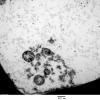

4 AXONAL DEGENERATION

3 Electron Microscopy